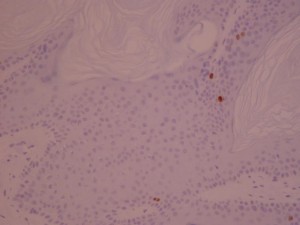

ki-67 staining of reticulo-acanthotic type of SKs.

ki-67 staining of reticulo-acanthotic type of SKs.

ki-67 staining of reticulo-acanthotic type of SKs.

ki-67 staining of reticulo-acanthotic type of SKs.